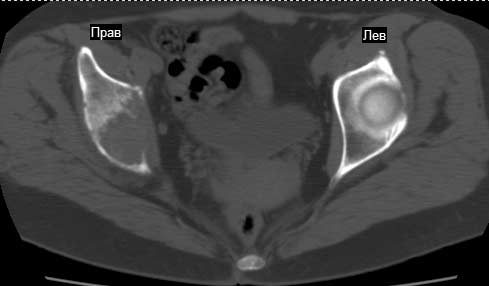

Сохранная по соматической патологии женщина ,47 лет. В 1996 г. установлен диагноз- cr левой молочной железы Т2N1Mo (2б)- проведено комплексное лечение- мастэктомия по Холстеду, ДГТ, 5 курсов ПХТ по схеме CMF. Сейчас менопауза уже 6-7 лет. В декабре 2004 года на профилактической остеосцинтиграфии с Тс99- выявлен единичный очаг повышенной фиксации препарата в зоне правой седалищной кости, рекомендована Рентгенография костей таза, выполнена- без патологии. УЗИ брюшной полости и Р-графия легких от конца апреля 2005 года - без патологии. Приблизительно 3 месяца назад появился болевой синдром в правом т/бедренном суставе с тенденцией к усилению. На рентгенограмме таза от мая 2005 года по заключению Рентгенолога очагов остеодеструкции не выявлено. Сегодня сделал ей Кт костей таза (картинки в приложении)- очаг деструкции в правой седалищной кости в зоне крыши вертлужной впадины.Что можно и нужно сделать? Жду советов, мнений, предложений по дальнейшей тактике ведения больной. С уважением, Корнев А.В.